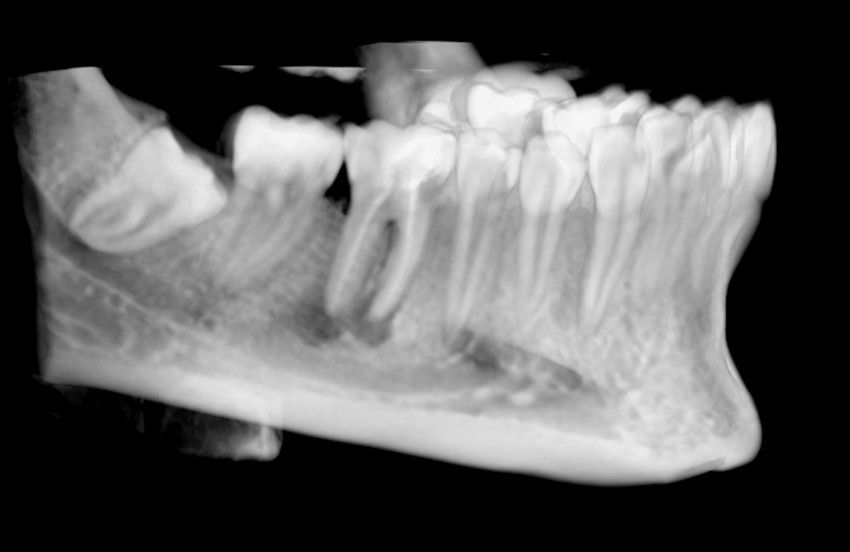

El sitio receptor debe garantizar la adaptación del diente donante, se realizará un diagnóstico mediante planificación con CBCT que permita segmentar virtualmente el diente donante y llevarlo digitalmente al sitio receptor3.

La confección de la réplica 3D del diente se ha de realizar con material biocompatible y esterilizable mediante radiación gamma y beta. La ventaja del modelo estereolitográfico es minimizar el tiempo extraoral del diente donante, el daño al ligamento periodontal, así como poder remodelar el alveolo receptor sin usar el diente donante5,13,14.

El autotrasplante dental es una opción terapéutica para aquellos casos en la que una pérdida dentaria es reemplazada por un diente donante del mismo paciente. Este autotransplante colocado en el alveolo puede ser inmediato o diferido. Suele estar indicado en paciente joven, siendo más frecuente el autotransplante de cordal a primer o segundo molar, y el de premolar a incisivo. El diente donante debe reunir unos criterios clínicos que aumenten el éxito de la técnica, basados en la morfología, el estadio de desarrollo radicular y la salud periodontal. La planificación se llevará a cabo con un CBCT y simulación virtual que genere un prototipo réplica en 3D; esto permite evaluar las dimensiones del diente donante para su correcta colocación en el alveolo receptor.

Se reporta el caso de un autotrasplante del tercer molar inferior derecho al alveolo postextracción de un primer molar inferior, en una paciente de 22 años de edad. Actualmente, el autotransplante se considera una opción de tratamiento si se siguen los criterios de selección del caso adecuados, y se realiza una técnica quirúrgica protocolizada. El diagnóstico planificado mediante CBCT, la simulación virtual y la confección de una réplica en 3D optimiza la técnica de forma segura, predecible con tiempos de cirugía menores.